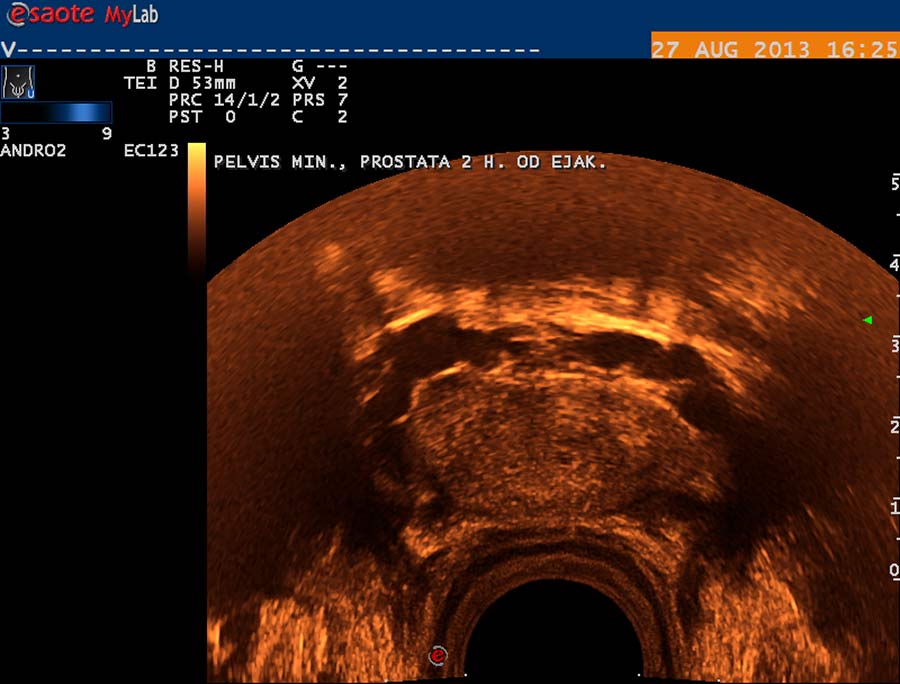

V případě druhém jde o kompresi ilických žil, které drénují vény z varlat probíhající podél chámovodů, a vény kremasterické, ústící do pánevních žilních pletení. Průběh žilní je však interindividuálně variabilní. Pleteň žilní pod bazí močového měchýře a okolo prostaty ( plexus venosus - labyrinthus Santorini) je velmi dobře vyšetřitelná transrektální USG. Používáme sondu o frekvenci 9 MHz se stejnými možnostmi harmonického zobrazení a Dopplerovské diagnostiky jako při vyšetření testes. Vény v okolí prostaty jsou dobře patrné v transverzální projekci na obr. 28, jejich ventrokaudální konvergence před prostatu je patrná na obr. 29, subprostatický průběh žil na obr. 30. Respirační reflux do těchto pletení je patrný na duplexním Dopplerovském záznamu – obr. 31, reflux v inspiriu a odtok v exspiriu na obr. 32. V kolmé projekci je patrný reflux při klidovém dýchání a při hlubším inspiriu na obr. 33. Přínos této diagnostiky pánevní žilní hypertenze bude v budoucnu užitečný při hodnocení žilní drenáže prostaty a žilní hypertenze v oblasti plexus venosus Santorini v souvislosti s významem hladin testosteronu a dihydrotestosteronu pro prostatu. Hladiny androgenů jsou v drenážní oblasti spermatických vén vyšší, nežli v periferní krvi.

obr. 28

obr. 29

obr. 30

obr. 31

obr. 32

obr. 33